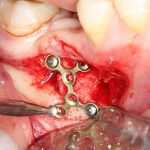

При горизонтальной остеотомии, на мой взгляд, удобнее использовать минипластины. Как я уже отмечал выше, в практике мы используем X- и H-образные минипластины под винты размером 0.9х4мм. Количество металла в разных условиях может быть разным — всё зависит от того, на каком этапе достигается полная неподвижность перемещенного костного фрагмента.

7. Заполнение образовавшегося пространства графтом.

В какой момент это делать? Наверное, если Вы используете графт в виде твердого блока, то, мне кажется. разумнее сначала уложить графт, затем проводить фиксацию перемещенного костного фрагмента винтами или минипластинами:

И наоборот, если вы применяете графт в виде гранул (типа, Bio-Oss L), то, для начала, нужно зафиксировать костный фрагмент, затем укладывать графт.